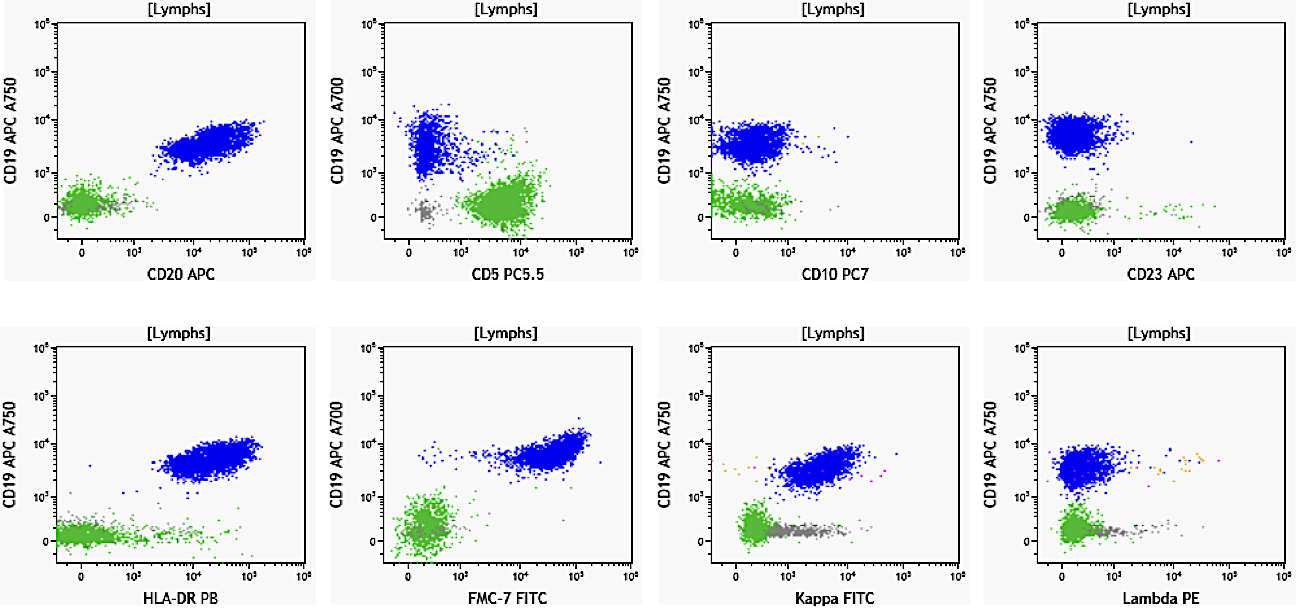

Flow cytometry description

Flow cytometry images

Contributed by Ling Zhang, M.D. and Caroline An, M.D.

- Immunophenotype of LPL cells: IgM+, CD19+, CD20+, CD22+, CD25+, CD10-, CD23-, CD103-, variable CD138

- Immunophenotype

- Positive: IgM, CD19, CD20, CD22, CD79a, CD25 and CD38 frequent expression

- Negative: CD5, CD10, CD103, CD23; however, CD23 expression is not uncommon in some cases